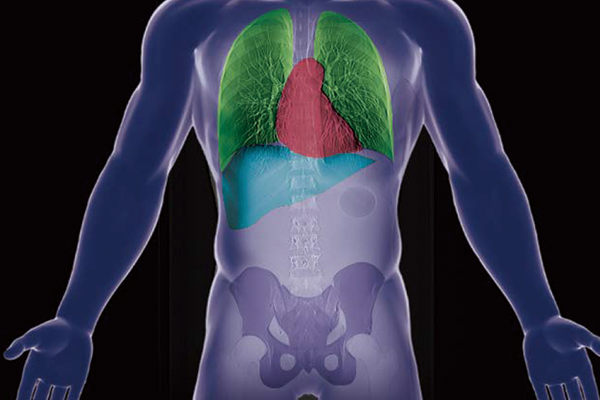

SYNAPSE 3D’s advanced image analysis technology aids clinical interpretation, reporting, and treatment planning. Especially, automatic organ segmentation technology enables fast and effective workflow, powered by REiLI, FUJIFILM's AI brand. With a series of high-tech applications developed in collaboration with clinical specialists, SYNAPSE 3D quickly and accurately delivers imaging result that promotes effective care collaboration.

REiLI makes it happen to extract organs and simplify your work.

Lung lobe

Liver

Kidney

Colon